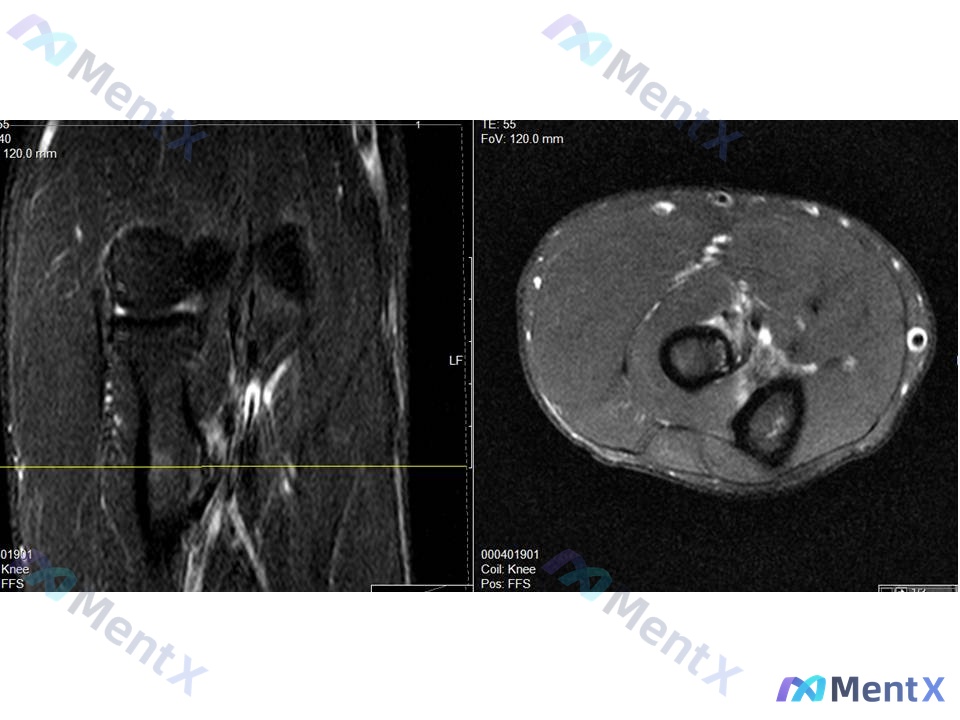

整理了一个挺有警示意义的病例,核心是「别被带偏,抓死核心体征」—— --- 病例基本情况 - 患者:35岁男性木匠 - 主诉:右肘前窝疼痛,用螺丝刀时明显加重 - 病程:6个月+,规范保守治疗(休息、抗炎、理疗)无效 关键体格检查 这个是破局核心: ✅ 钩试验(针对桡神经浅支卡压)正常 ❌ 但抗旋后...